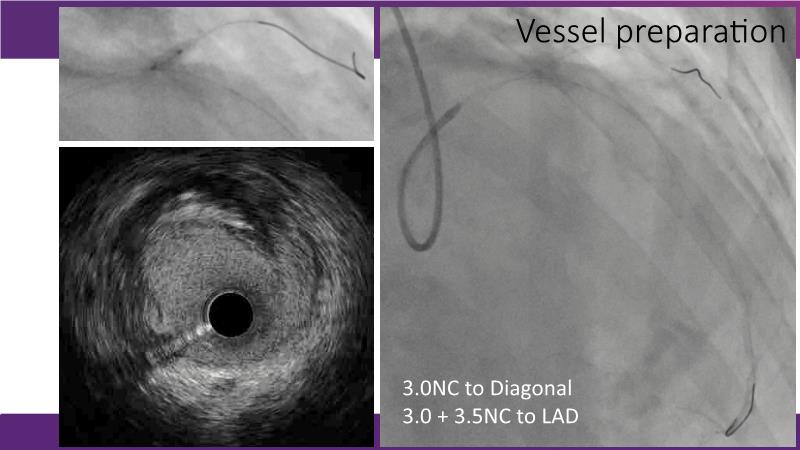

Through the study of two cases, this session examines the need for stenting bifurcation lesions and the role of DEB technology in avoiding stent-related complications in long diffuse disease. It emphasizes the benefits of SELUTION SLR balloons for de novo lesions, discussing how sustained limus release technology can broaden DEB indications and reduce metal usage, understanding the limitations of DES and the emerging role of DEB with sustained limus release, and learning how to identify dissections that can be left unstented.